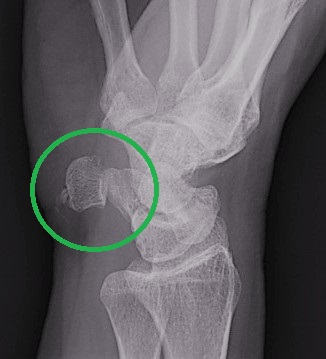

L’échographie s’avère nécessaire pour visualiser les tendons, épanchements, cartilages, muscles, de manière rapide et efficace. Mais la radiographie est fort utile en complément, car elle permet une analyse des os et des articulations.

Exemple : Tendinopathie calcifiante de l’ulna confirmée en radio